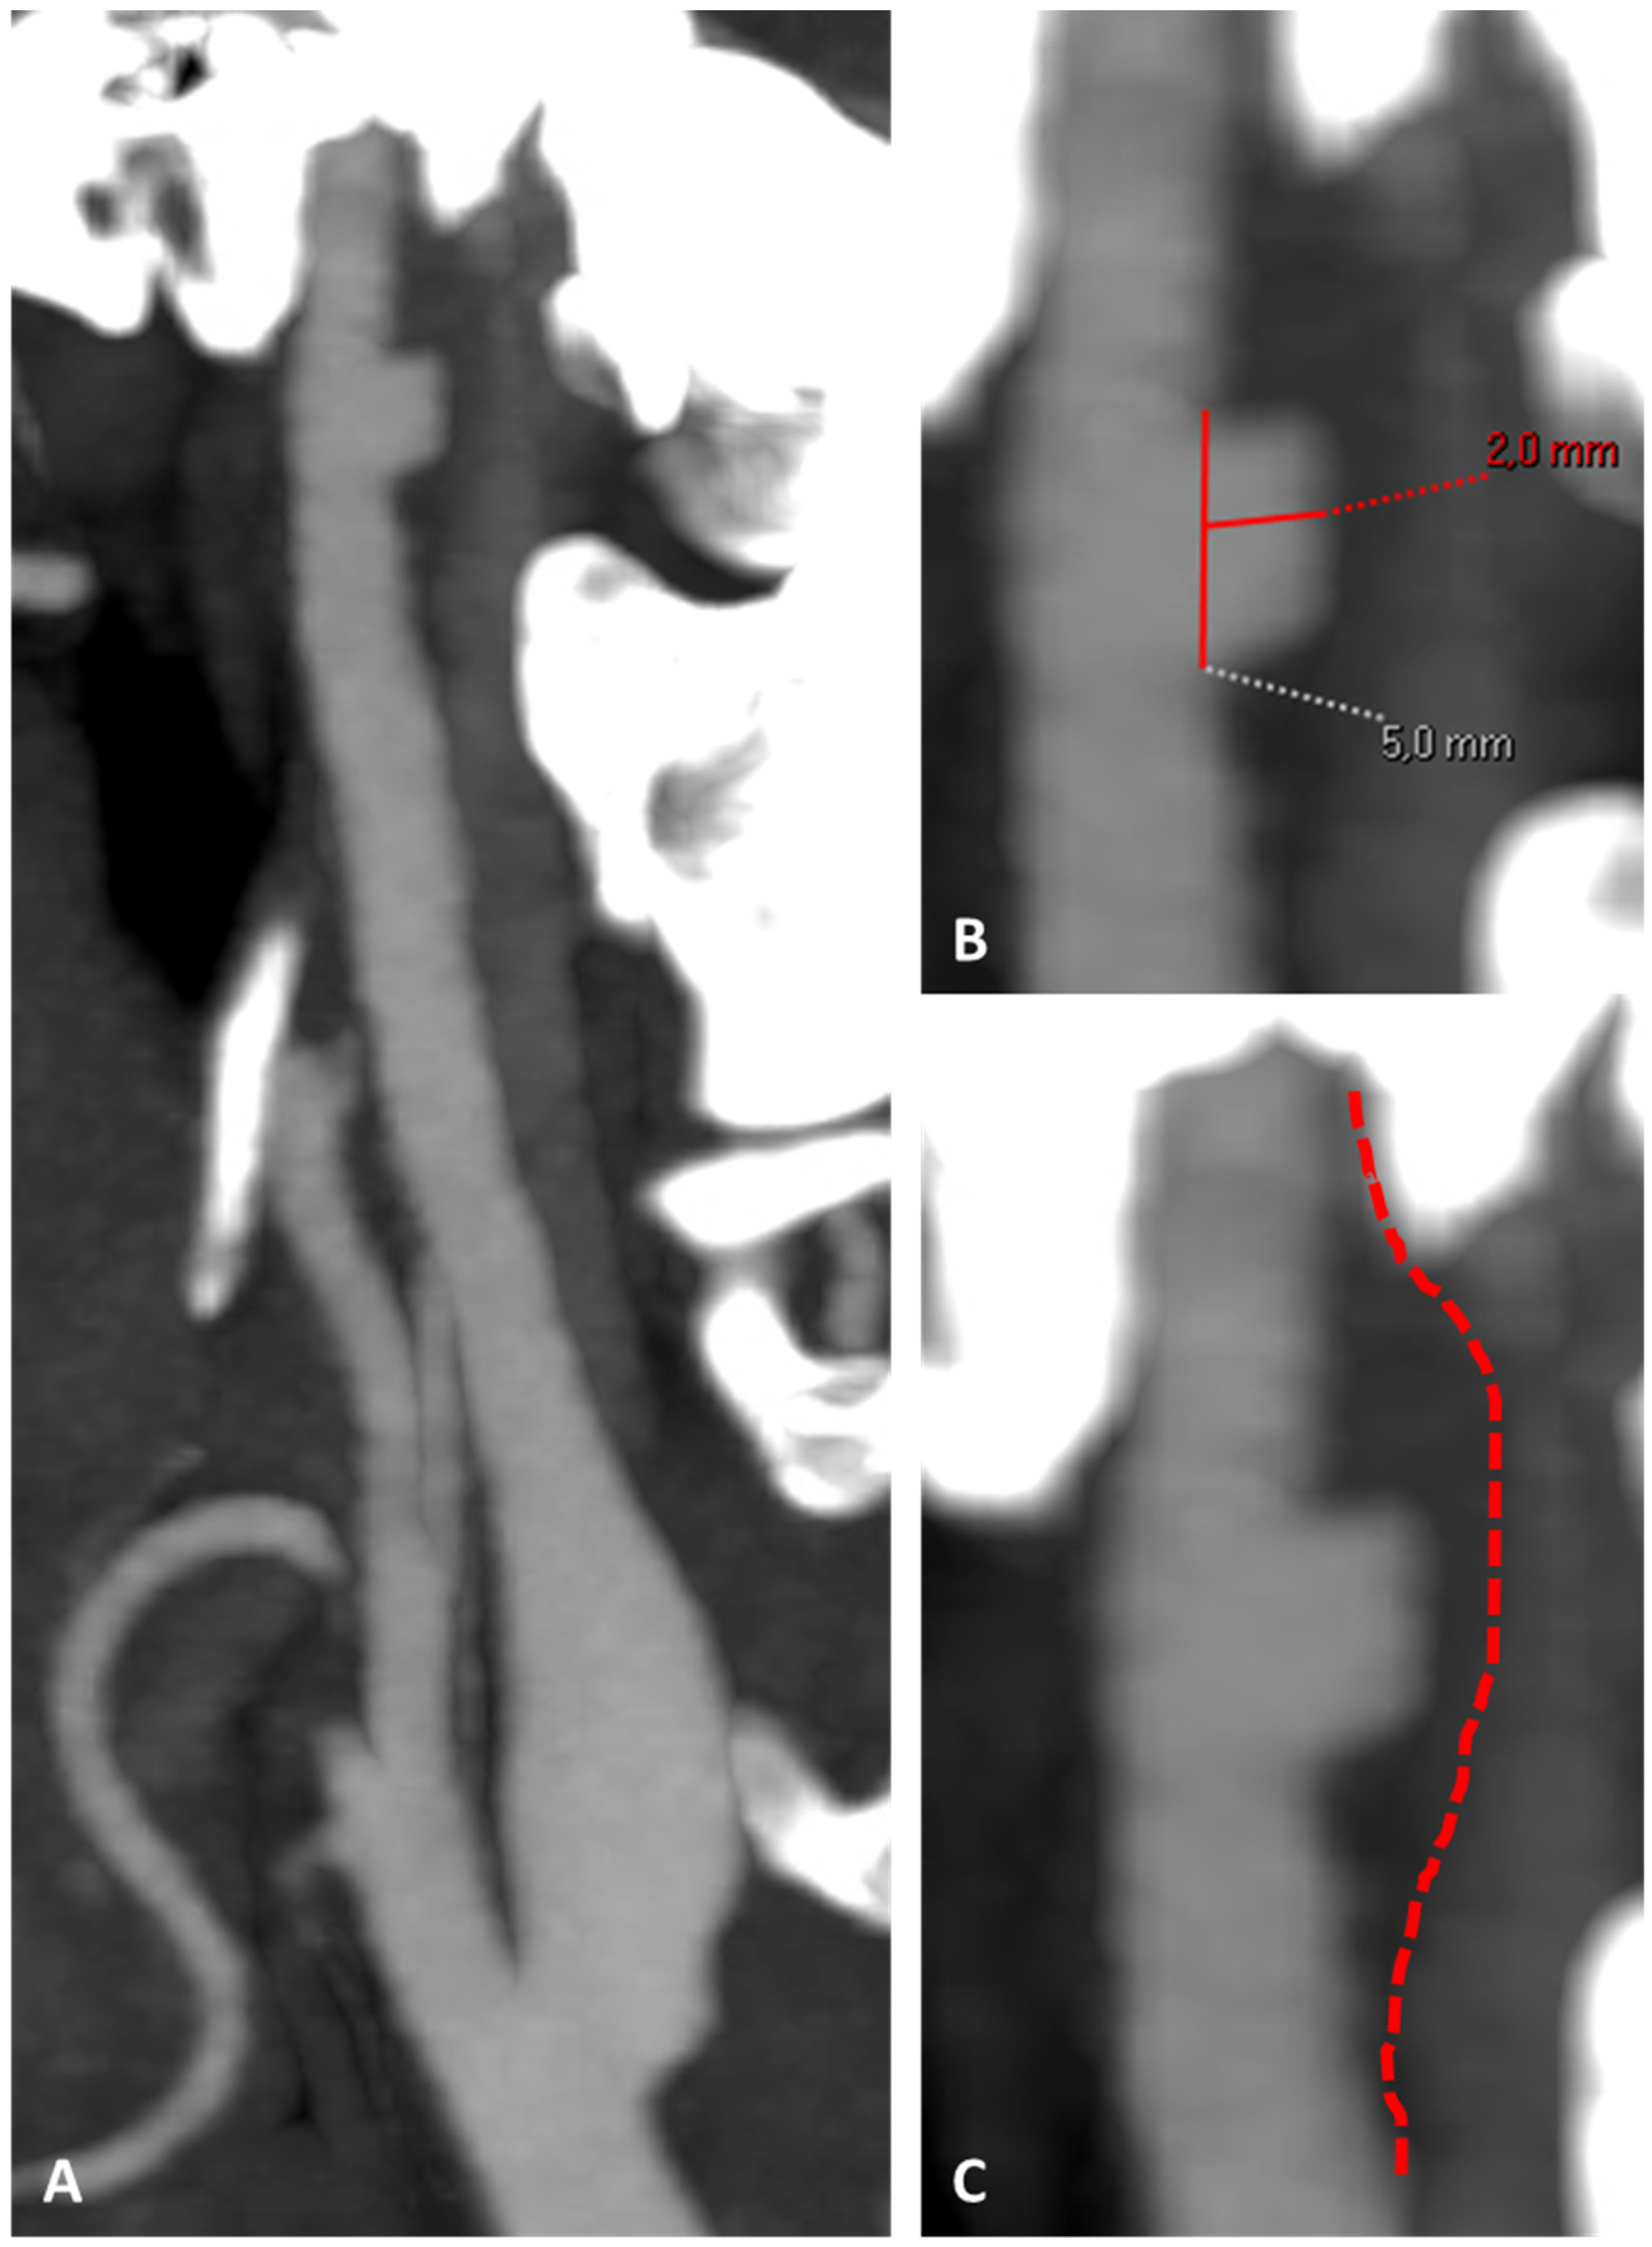

3.1. Case 1